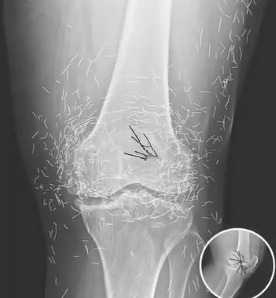

Doctors Shocked by What They Found Inside Woman’s Knee During Routine X-Ray

A 65-year-old woman in South Korea visited the hospital expecting confirmation that her swollen, painful knees were due to arthritis.

Instead, X-rays revealed something shocking—her joints were filled with hundreds of tiny gold needles.

The discovery stunned doctors and exposed the dangers of an extreme, little-known variation of acupuncture.

this version involved implanting thin gold needles permanently, with the belief they would provide constant pain relief.